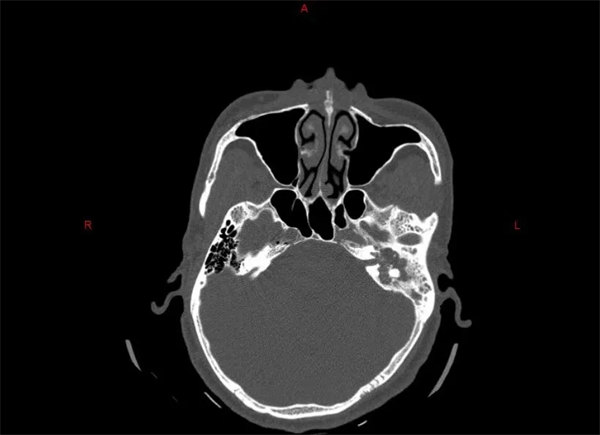

患者白先生(化名),近兩年來因為左耳反復流膿、聽力下降,近3個月又出現左眼閉合不全的癥狀,隨來我院耳鼻喉科就診。科室為其行顳骨CT檢查,結果顯示:患者左側顳骨巖部迷路上型膽脂瘤,侵犯左側內聽道底、耳蝸、前庭、鼓室、乳突、中顱窩底。耳鼻喉科副主任醫師章松林帶領團隊認真完善術前準備,精心設計手術方案,計劃為患者實施經耳蝸徑路左側巖部膽脂瘤切除、耳大神經移植面神經修復、腹部取脂肪左側中耳封閉術。

手術如期開展,術中見患者左側顳骨巖部膽脂瘤,侵犯范圍與術前評估基本相符,膽脂瘤包裹面神經垂直段、錐曲段、水平段及膝狀神經節,其中水平段與膝狀神經節處破壞顯著,遂取耳大神經橋接面神經。術后患者順利出院繼續面神經康復訓練。